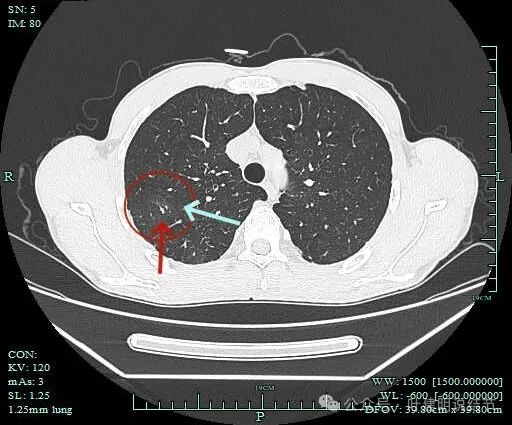

病灶2:

病灶出现,密度杂乱。

有磨玻璃成分,且轮廓清,磨玻璃边缘有细毛刺征,实性成分的边缘毛糙不平,形态不规则。

灶内有僵硬支气管走行,边上少许磨玻璃成分,病灶有一定收缩力。

灶内支气管穿行且显得僵硬。

胸膜牵拉,灶内支气管通气征并显僵硬,部分边缘有毛刺征。

有血管进入并异常增粗;病灶有分叶征,有毛刺征,也有胸膜牵拉征。

病灶有细毛刺征,感觉有收缩力。

实性成分为主,边上少许磨玻璃成分。

叶间胸膜牵拉。

这个病灶是非常典型的恶性的,总体上基本上是实性成分,但边上仍有少许磨玻璃,而磨玻璃成分有分叶与细毛刺,病灶内部有支气管通气征,且支气管显僵硬,又有异常增粗的血管进入。再加上胸膜牵拉、叶间裂牵拉,整体轮廓较清,周围肺野清爽,没有卫星灶。所以基本上就是浸润性癌了的。